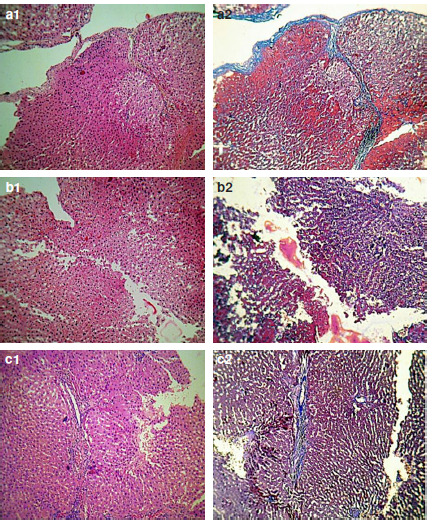

Materials and methods: The aerial parts of this plant were macerated for 2 days using methanol. After anesthesia and laparotomy of 12 female Wistar rats (120-220 g), the liver was exposed and two incisions were performed for bleeding. One was packed by sponge with A. millefolium and another without A. millefolium as a control group. Animals were divided into two groups that A. millefolium (150 mg/kg) was used in the first incision for one group and in the second incision for another. Liver biopsy was taken after 4, 6, and 8 weeks.

Results: We observed that usage of A. millefolium for liver incisions, either in the first incision or in the second incision; bleeding time decreases significantly (36.1% and 31.9%, respectively). Histopathological evaluations revealed no signs of toxic and hepatic damage for periods 4, 6, and 8 weeks in the female rats.